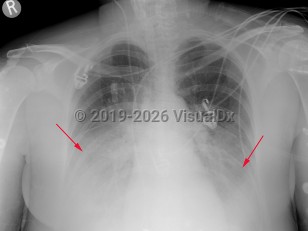

Viral pneumonia